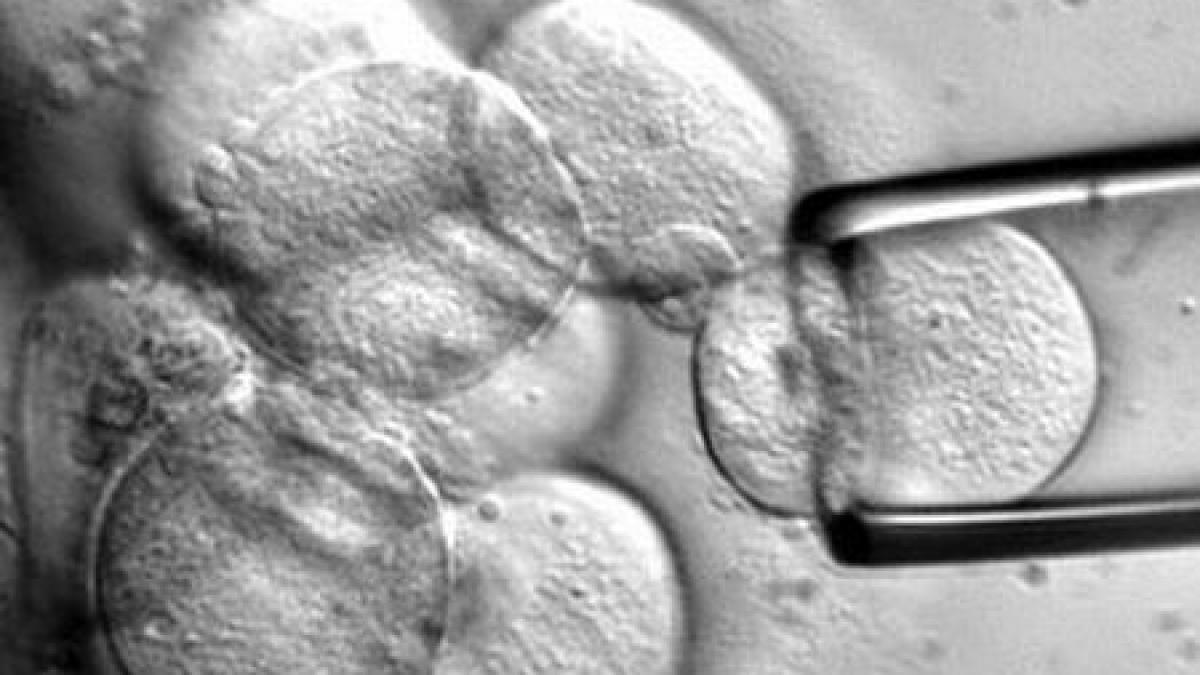

Foto: www.scientificamerican.com

Prima bancă de celule stem într-un spital de stat a fost înfiinţată la Institutul Clinic Fundeni. Ea îndeplineşte în totalitate standardele Agenţiei Naţionale de Transplant şi pe cele europene care reglementează activitatea de procesare şi conservare a celulelor vii.